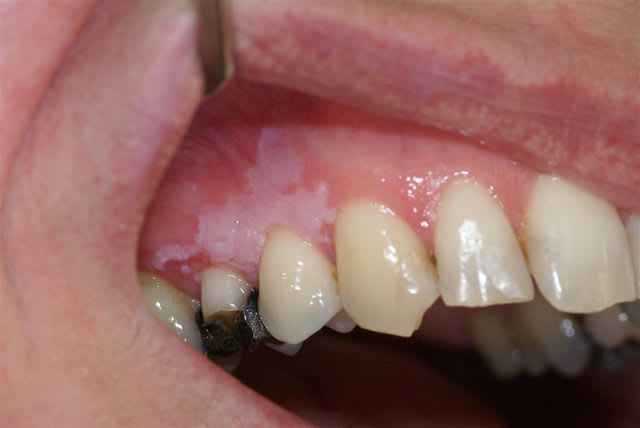

pas de douleur, pas de saignements, bords irréguliers, depuis plusieurs mois, 1ére consultation, légèrement ulcéreux en regard de la 15.

pas du tout c est une tres classique leucoplasie homogene . Ca demande un certain suivit. Effectivement si tu n ' as pas l habitude adresse.

C'est surtout l'ulcération qui interroge: soit elle est d'origine traumatique et doit cicatriser sans traitement sous 15 jours -> dans ce cas surveillance semestrielle du lichen, soit elle ne cicatrise pas et alors c'est biopsie sans attendre.

Surtout ne rien prescrire: il faut voir si la lésion cicatrise seule ou non.

Apparemment la 15 portait une couronne: un galvanisme peut-être à l'origine du lichen.

De plus la perte de la couronne entraîne la perte du bombé vestibulaire et de sa déflexion alimentaire qui pourrait expliquer la blessure traumatique de la gencive.

Hypothèse à vérifier.

Et le gagnant est Tillc :

résultat de l'examen histo : leucoplasie marquée, homogène, inflammation chronique du chorion.

N'ayant pas l'habitude du suivi de ce genre de lésion, j'adresse au stomato.